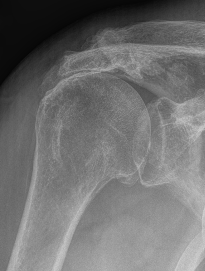

Xray

Look for: acromial morphology / high riding humeral head / rotator cuff arthropathy

Acromial spur / superior migration humeral head / rotator cuff arthropathy